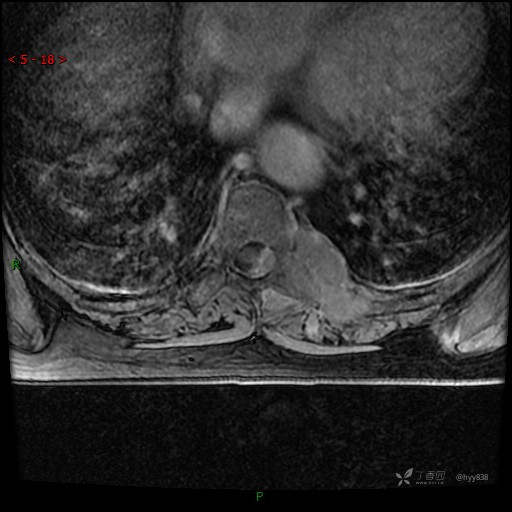

MRI CE